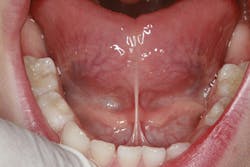

Example of a tight lingual frenum restricting movement of the tongue:

The treatment for these symptoms included myofunctional therapy and a lingual frenulectomy. A myofunctional therapist is typically a speech pathologist or hygienist who has undergone additional training to help correct issues related to mouth breathing, tongue posture, and tongue habits. A listing of myofunctional therapists can be found at www.myoacademy.net, which is the website for the Academy of Orofacial Myofunctional Therapy. There seem to be a lack of trained myofunctional therapists - we need more!

We started my son on some myofunctional exercises to help strengthen and stretch his tongue prior to the frenulectomy. We then used a laser to release the frenum. Oftentimes this needs to extend deep into the fibrous tissue in order to get the necessary functional benefit. Due to the highly vascular nature of the tongue, this is a procedure to be careful with. Directly after the release of his frenum, we did some stretching exercises to help ensure the frenum did not reattach. Again, the degree of tongue-tie can vary. A posteriorly tight frenum can present problems and requires a more technique-sensitive frenulectomy.